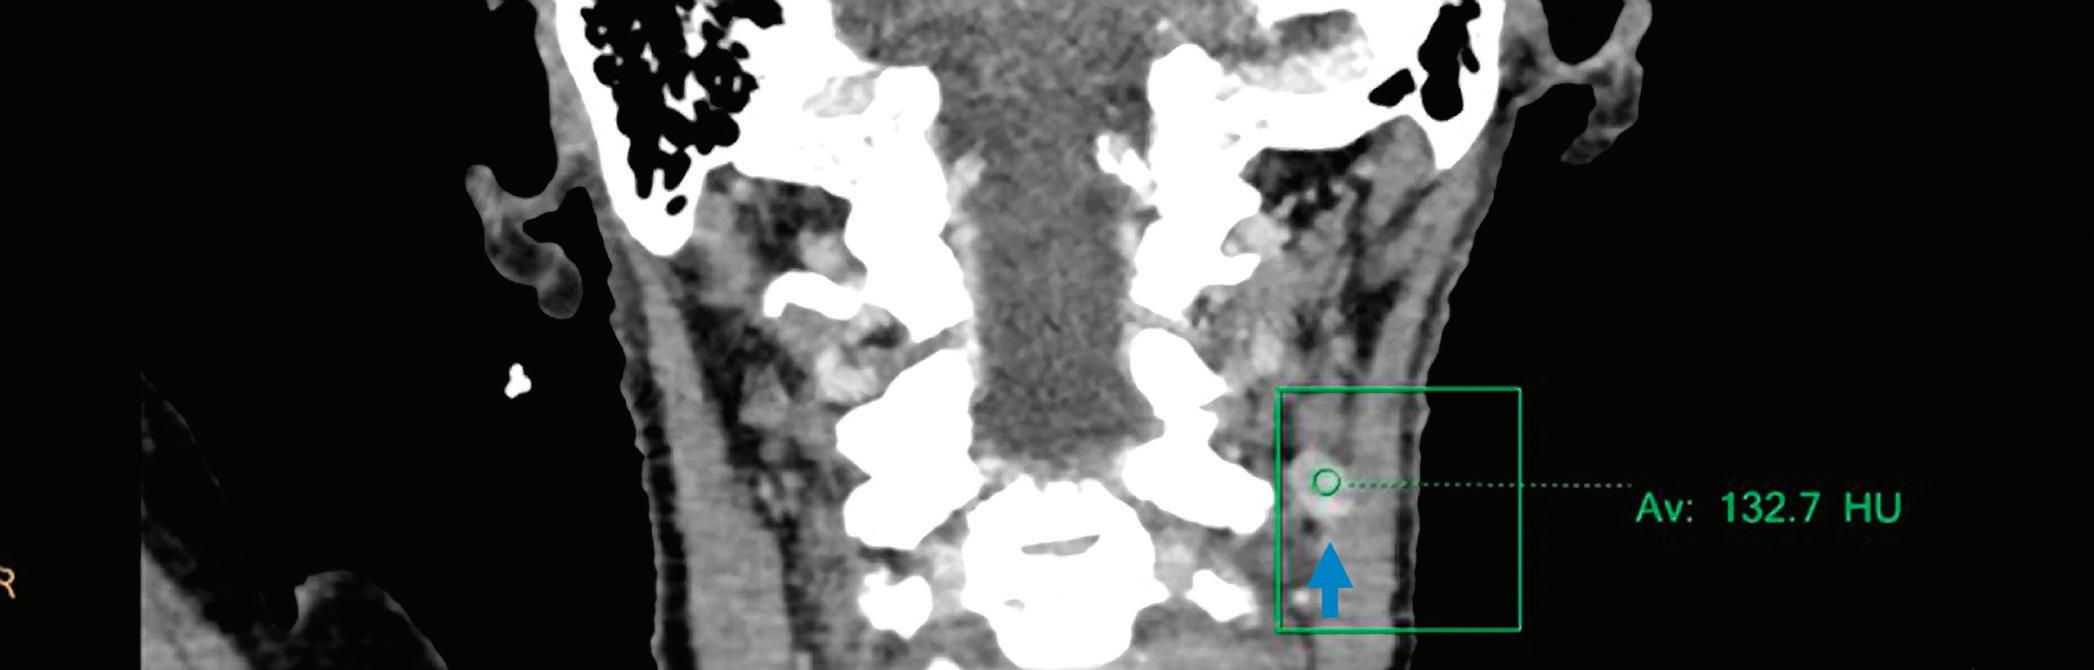

Conventional CT with contrast, coronal image at 120 kVp: left level IIa enlarged lymph node (arrow) with an attenuation value of 132.7 HU.

Conventional CT with contrast, coronal image at 120 kVp: left level IIa enlarged lymph node (arrow) with an attenuation value of 132.7 HU.